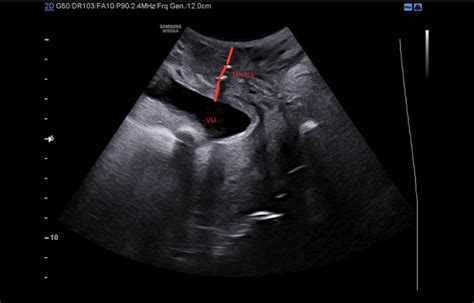

Evaluarea riscului de naștere prematură se realizează prin măsurarea colului uterin, o structură ce menține uterul închis. Cu cât colul uterin este mai lung, cu atât riscul de naștere prematură este mai mic.

Cum se Măsoară Colul Uterin?

Măsurarea colului uterin se efectuează printr-o ecografie transvaginală, metodă considerată fidelă și sigură pentru făt. O măsurătoare a colului de peste 25 mm indică un risc scăzut de naștere prematură, în timp ce un col mai scurt de 25 mm presupune un risc crescut. În cazul unui col uterin scurt, există soluții terapeutice, precum administrarea de progesteron sau cerclajul colului uterin.